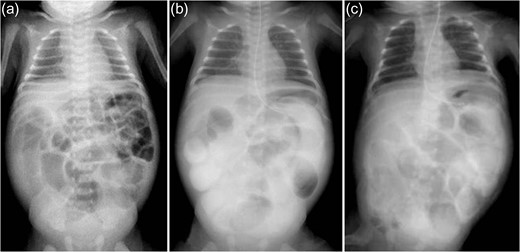

A 21-day-old boy with vomiting, abdominal distention and feeding intolerance presented to our institution. He was born at 36 weeks and 6 days of gestation, weighing 2220 g, with Apgar scores of 8 at 1 min and 8 at 5 min. For the first 4 days of life, he was both breast- and formula-fed. After hospital discharge, he was exclusively breast-fed. He experienced occasional vomiting until 19 days of age, when he developed frequent vomiting. When he was 20 days old, he was taken to the doctor for several days of watery stools, a single episode of bilious vomiting, and feeding intolerance. He was admitted to a local hospital at a weight of 2685 g. Abdominal radiography showed partially dilated loops of bowel with intestinal gas (Fig. 1a), and a gastric tube was inserted for frequent vomiting. At the age of 21 days, he was transferred to our hospital for further examination. A gastrointestinal X-ray series and an enema revealed gastric volvulus and gastroesophageal reflux, without intestinal malrotation or a change in intestinal caliber. We admitted the patient for observation. The following day, an abdominal radiograph showed complete passage of contrast, which indicated the absence of intestinal atresia or obstruction. However, the volume of bile discharged through the gastric tube was gradually increasing, and he had little passage of feces, even with a glycerin enema. We decided to re-evaluate for intestinal obstruction and injected contrast into the gastric tube. Follow-up abdominal radiography showed obvious intestinal dilation with gas and retention of the contrast medium (Fig. 1b and c). Based on his clinical course and radiological findings, we suspected distal intestinal obstruction. When the patient was 24 days of age, we performed laparotomy, which revealed a caliber change in the ileum with a stricture ~10 cm proximal to the ileocecal valve (Fig. 2a). A 6-cm length of bowel around the stricture site was resected, and an end-to-end anastomosis was performed. On gross findings of the resected specimen, the lesion was noted to be 1.5 cm in length, featuring a stricture and erosion/ulceration (Fig. 2b and c). On microscopic examination, the margins of resection showed <20 eosinophils per high-power field (HPF) (×400) (Fig. 3a). However, mucosal eosinophilia was recognized in distant position from the ulcer (Fig. 3b and c). The presence of eosinophil accumulation in the lesions presented more than 20 eosinophils per high-power field (HPF) (×400). The eosinophils were oriented towards the epithelium and diffusely distributed throughout the tissue. In the stenotic portion of the specimen, the layers between the mucosa and the muscularis propria were notably absent, and granulation and fibrotic tissues were found (Fig. 3d).

Abdominal radiography. (a) Admission films show partially dilated loops of bowel with intestinal gas (age 20 days). (b and c) Time progression radiography. Five hours after injecting contrast through a gastric tube (b, age 23 days) and 16 h after injecting contrast medium (c, age 24 days); dilated loops of bowel with intestinal gas are visible, with residual contrast medium.